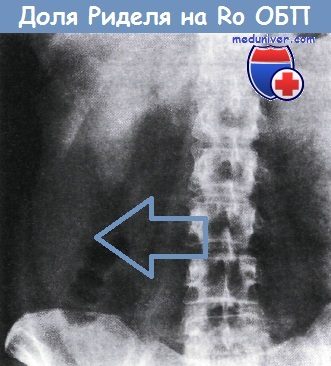

Как выглядит доля Риделя на УЗИ печени